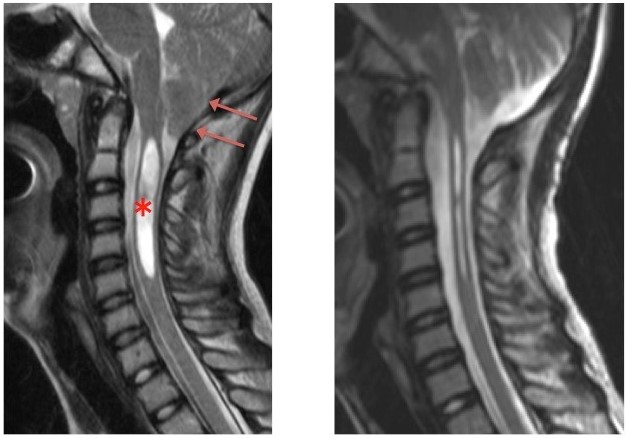

図1 キアリI型奇形の術前(左側)及び術後(右側)のMRI画像 矢印は下垂した小脳扁桃を、*印は脊髄空洞症を示しています。術後脊髄空洞症が改善していることが分かります。